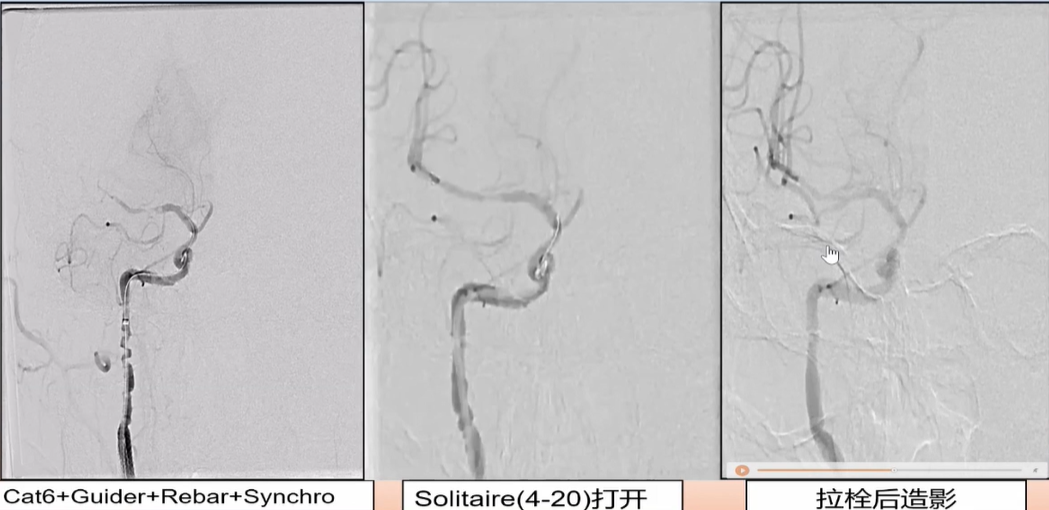

接下来处理远端,Synchro微导丝与Rebar微导管的辅助下,选择置入Solitaire(4-20)支架,支架打开后使用抽拉结合的方式使血管再通。

过程影像

病历夹什么径技·第152期|串联营病历夹:川陕大营_https://www.jmylbn.com_新闻资讯_第89张

取栓后造影如下: